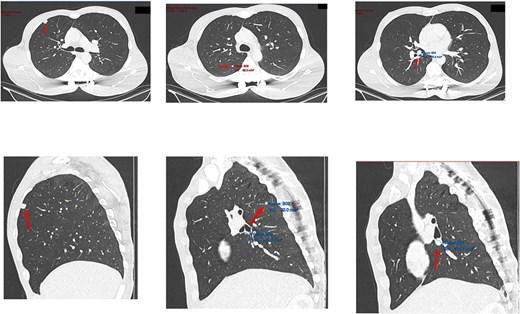

Subsequent computed tomography (CT) scan and positron emission tomography (PET) scan (Figs 2 and 3) confirmed the presence of three nodules in the right lung, suspicious for sarcoma metastases. An anterior, pleural-based upper lobe lesion, a posterior lower lobe lesion, and a lesion located at the bifurcation of his right middle and lower lobes.

Transverse and saggital views of the three nodules identified on an investigative CT scan.